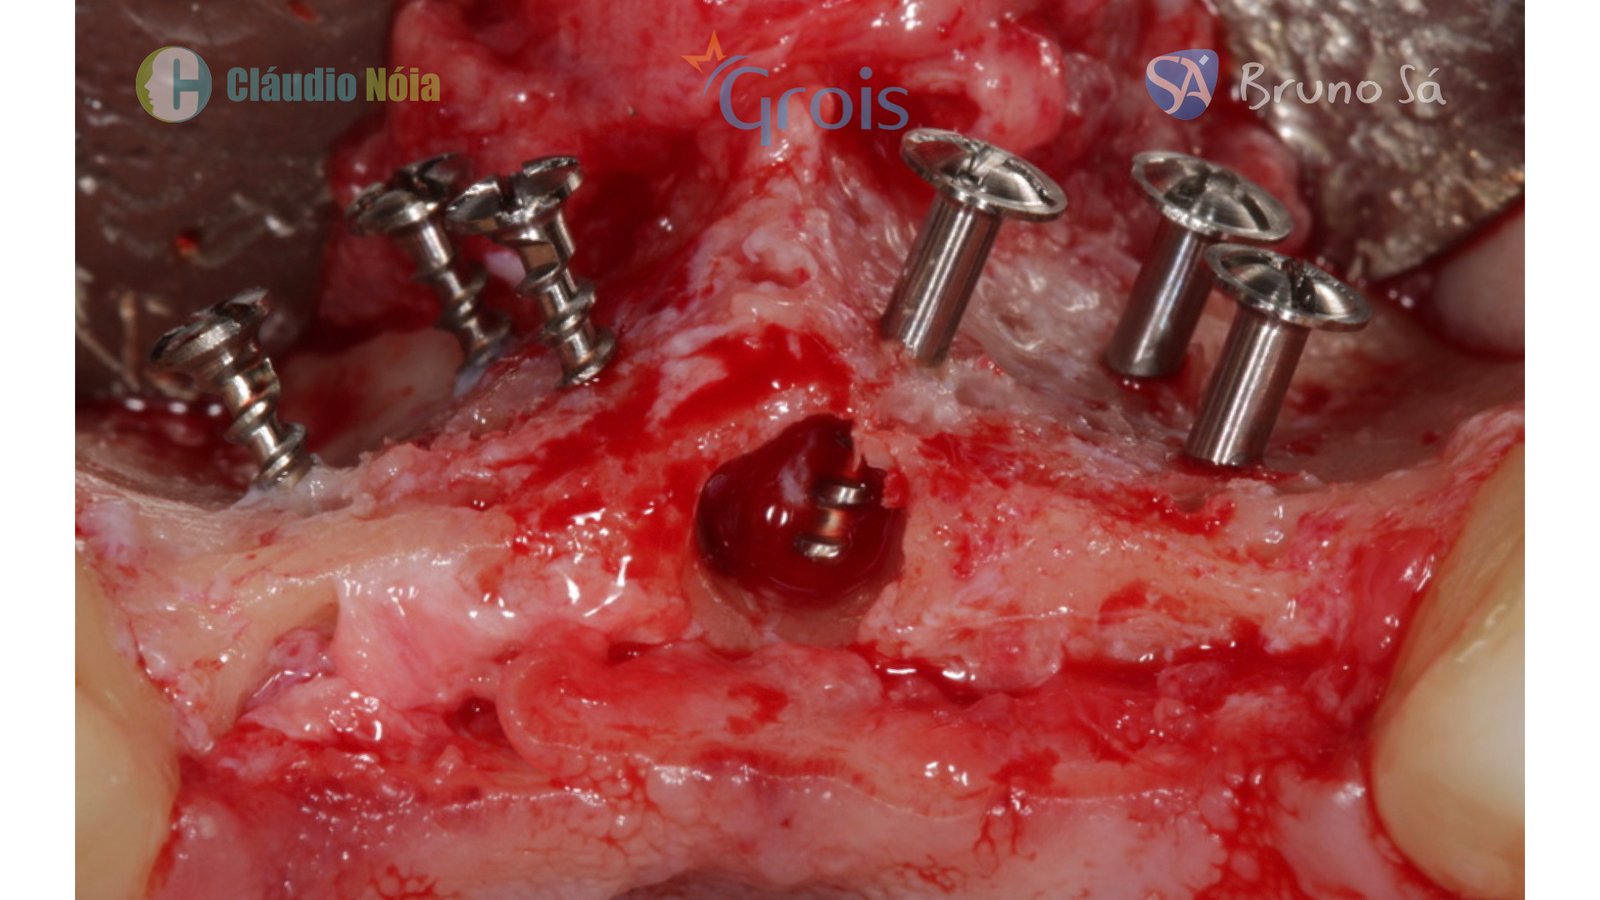

Para realização da técnica Screw Tent Pole são utilizados parafusos que funcionam como tenda para suportar o tecido mole, bem como são utilizados biomateriais e membrana de colágeno (ou Fibrina Rica em Plaquetas-PRF) visando promover a neoformação óssea.

Paciente apresentou-se a Área de CBMF da Instituição com a pré-maxila edêntula (Figuras 1, 2 e 3) e foi submetido a técnica Screw Tent Pole utilizando os parafusos da linha Orth – Implacil de Bortolli (Figura 3). Do lado direito da pré-maxila foram instalados 3 parafusos que apresentavam roscas em toda superfície, enquanto que do lado esquerdo foram instalados 3 parafusos que não apresentam roscas no terço cervical (Figuras 4, 5, 6, 7 e 8). Biomaterial associado com PRF (Stick Bone) foi adequadamente acomodado na região e recoberto por membranas de PRF (Figuras 9, 10 e 11). Uma sutura livre de tensão foi realizada para finalizar o procedimento cirúrgico (Figuras 12 e 13).